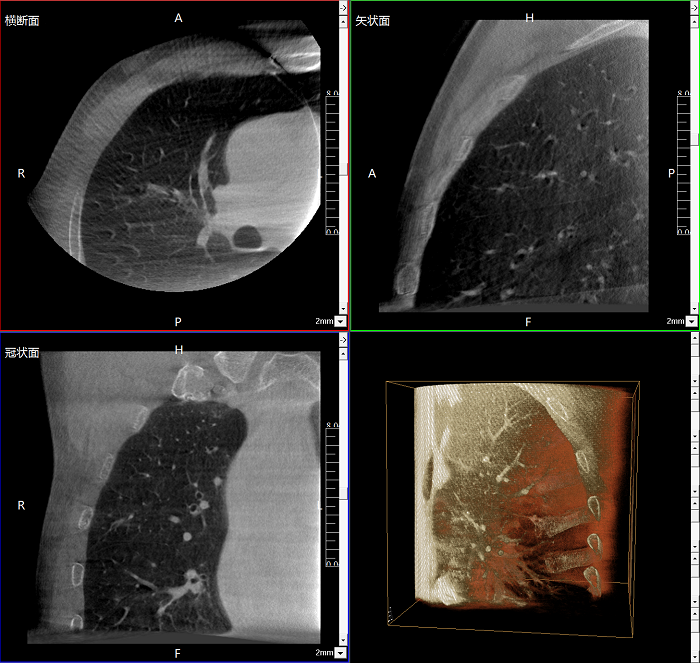

三維成像 全面觀察

任意視角、任意切面觀察

術(shù)中實(shí)時(shí)生成橫斷面、矢狀面、冠狀面及三維影像,可在任意切面、任意角度評估植入物和解剖結(jié)構(gòu)的相對位置。

術(shù)中CT檢查 減少翻修概率

通過術(shù)中三維影像的檢查,可以立即發(fā)現(xiàn)植入物的錯(cuò)位,減少不必要的第二次手術(shù),減少并發(fā)癥概率以及感染風(fēng)險(xiǎn)。